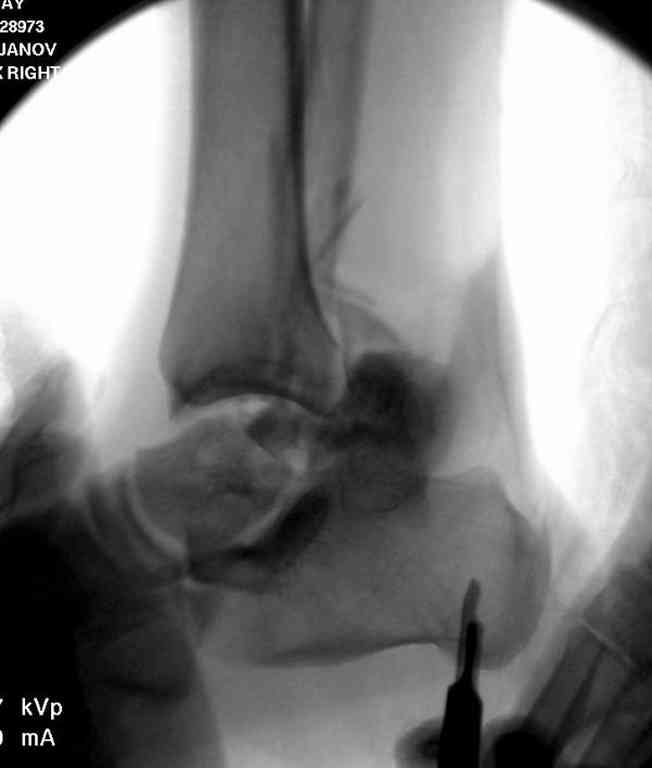

Второй случай прооперирован вчера.

10 дней назад поступил с открытым повреждением медиальной лодыжки и переломо вывихом таранной кости. Ургентно сделана репозиция с наложением наружного фиксатора + Irrigation&Debridment.

Во время репозиции выявили повреждение заднего сухожилия м. тибиалис и задней большеберцовой артерии. Медиальную рану удалось закрыть частично и установлен вакуум.

Дважды провели Irrigation&Debridment с заменой вакуума.

Вчера провели фиксацию.

Из-за многооскольчатости дистальной части малоберцовой, где невозможно было провести фиксацию шурупами, перелом зафиксирован подпирающей пластиной, которая должна служить дополнением отсутствующей дистальной части малоберцовой (lateral cortex substitute).

Для стабильности два шурупа на синдесмоз.

Медиальную рану с приближенными краями продолжаем вакуумировать (KCI). Наружный фиксатор оставлен на пару недель, надеюсь, небольшая рана будет гранулировать и закроется без кожной пластики. Фиксация медиальной ложыжки не планируется.